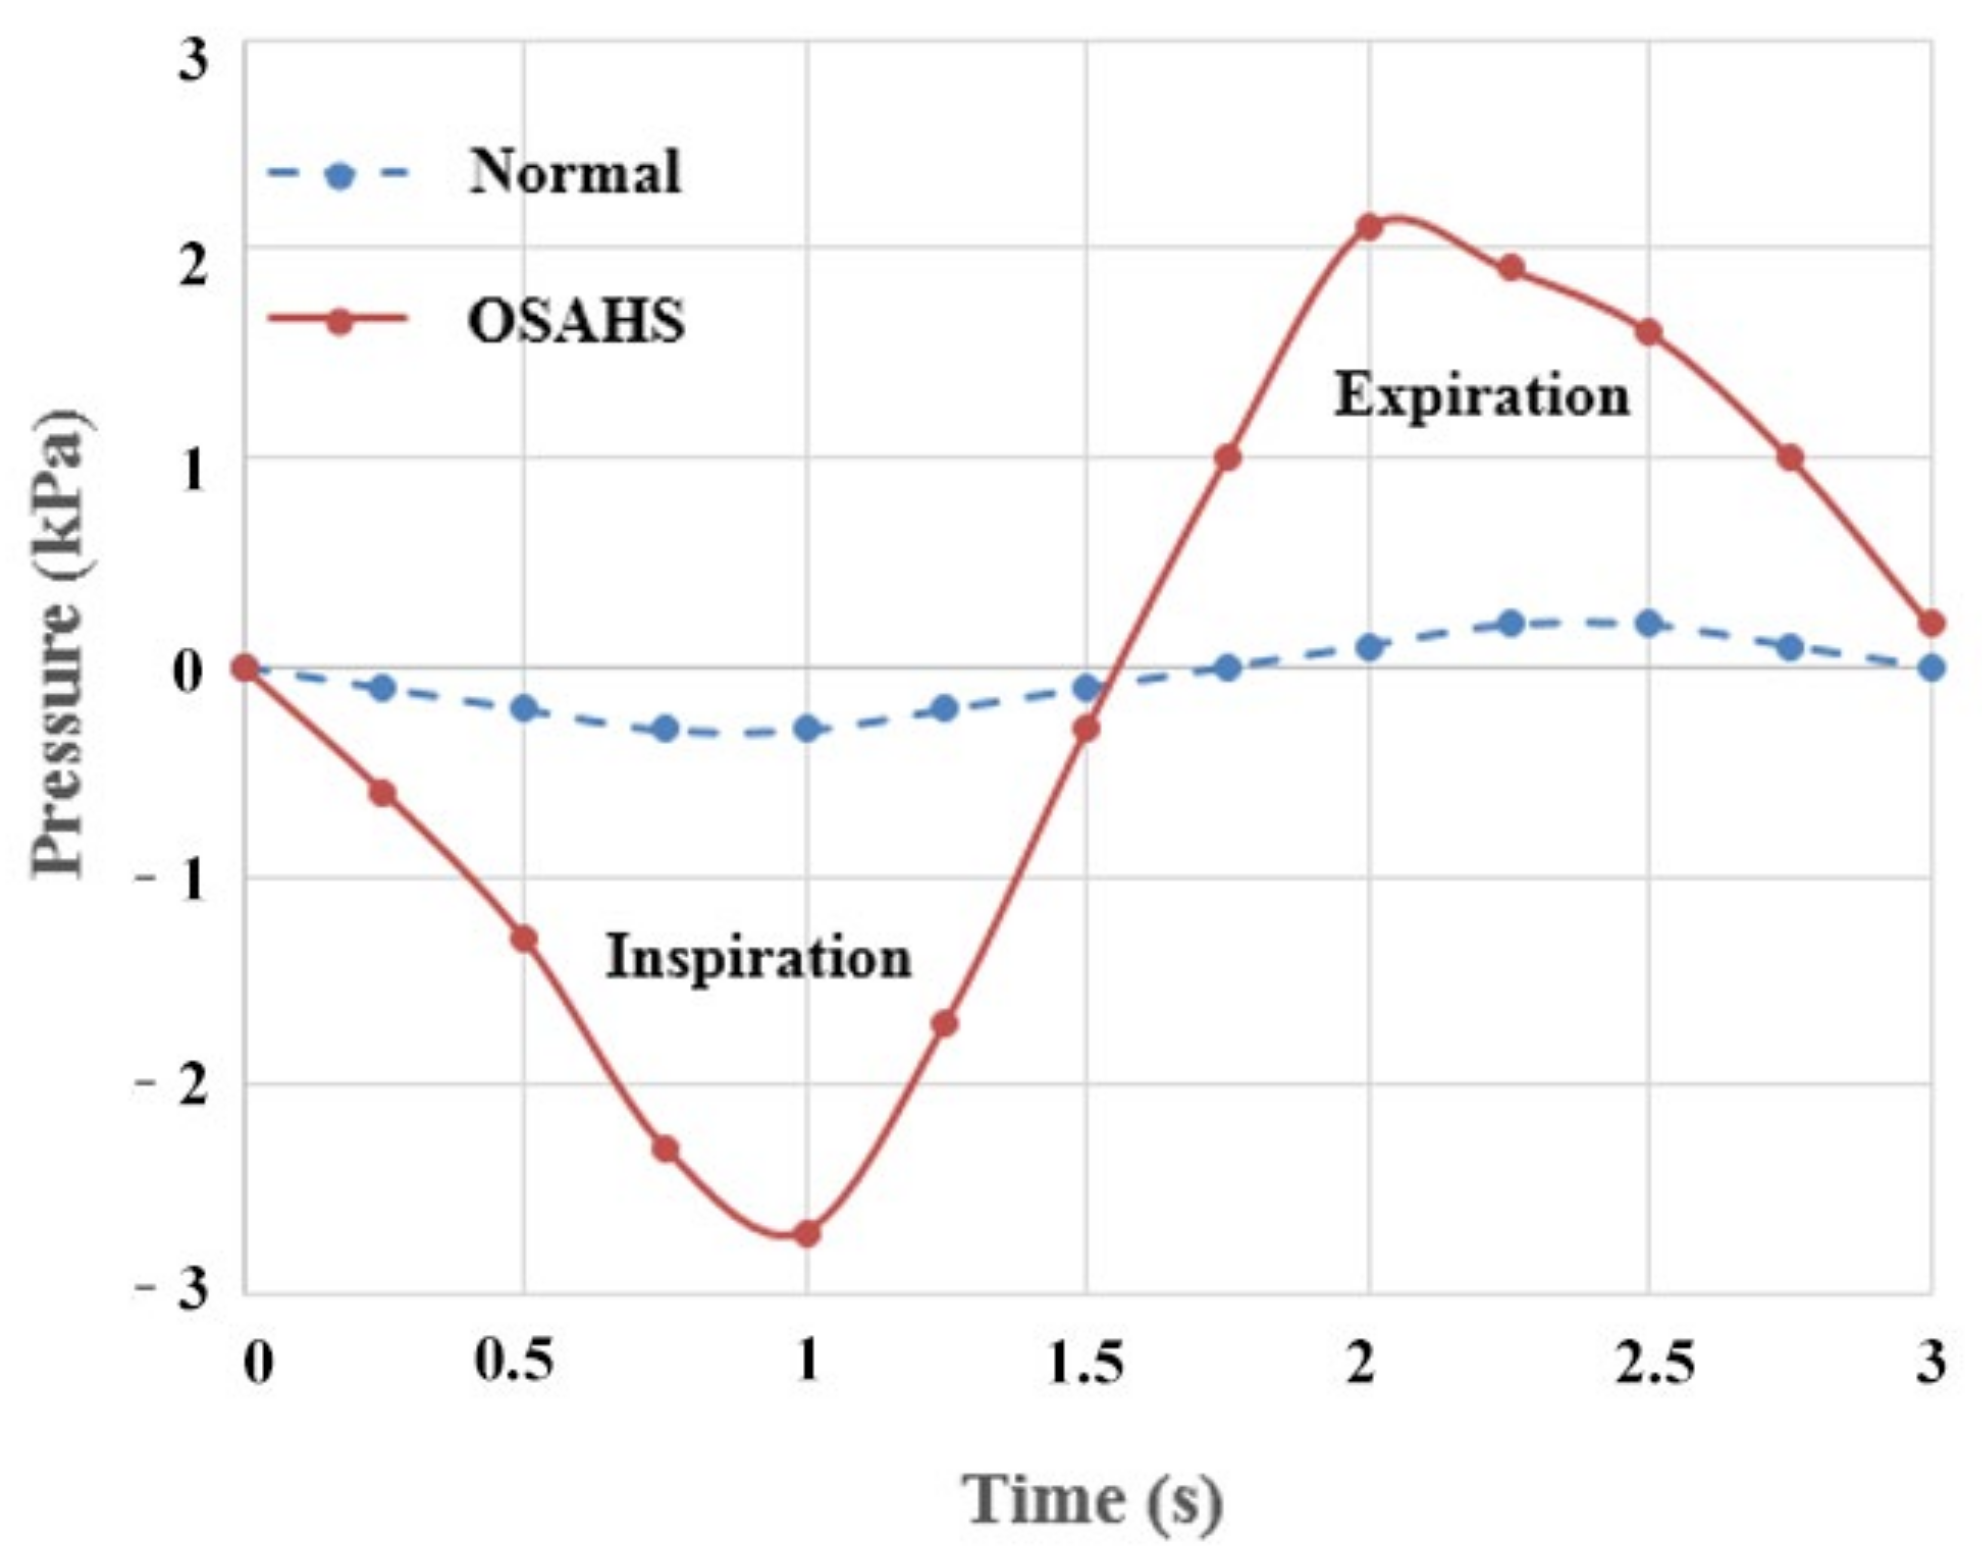

2.1.2. Clinical Monitoring of Cavity Pressure

- The airflow characteristics during the inhalation phase are noticeably different from those in the exhalation phase for both eupnea and apnea. As the OSAHS patient breathes, the minimum pressure occurs alternately between the soft palate and the anteroposterior wall of pharynx, which causes the soft palate to vibrate during respiration, and therefore, the patient snores in sleep.

- The soft palate in pharyngeal cavity would exerts a one-way valve effect and collapses in the exhalation phase if the patient sleeps in the supine position, regardless of eupnea or apnea.

- The mechanical environment of the airway is directly dependent on the action of the airflow. If the mechanical properties of the soft palate remain unchanged, the pressure makes the soft palate collapse in apnea. In eupnea, the pressure allows the airflow to pass freely through the airway.